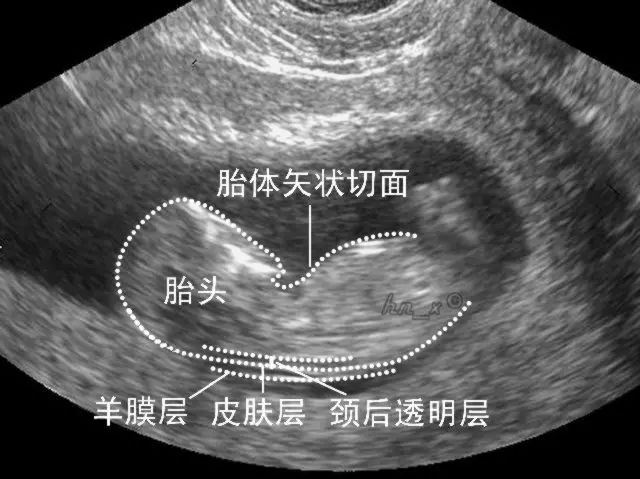

孕10~14周检查,建议在孕11-13+6周进行。

NT检查实际上是胎儿颈项透明层检查,是指胎儿的颈项背部皮肤层与筋膜层之间软组织的最大厚度,属于孕早期的筛查项目之一。

(图:NT检查的正常与异常的比较)

在国内,NT检查和唐筛是分开进行的,而在国外,两者是一起做的。NT检查除了抽血,还要做超声的检查,在超声下除了量NT值大小外,也需要看静脉导管是否有反流或缺失,鼻骨是否有缺失,三尖瓣是否有反流、四肢是否出现重大异常、膀胱是否过大等。NT检查综合抽血、超声检查、病史(包括个人病史和家族病史)、孕妇血压等情况,最后才得出结果。